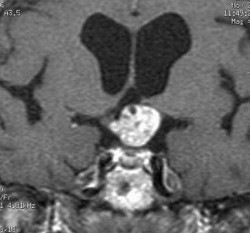

MRT eines intra- und suprasellären Kraniopharyngeoms mit dem typischen unregelmäßigen Aspekt. Man sieht gut die zentrale Lage im Bereich der Hypophyse und des Sehapparates

Die bildgebenden Verfahren der Wahl sind beim Kraniopharyngeom die Kernspintomografie (auch Magnetresonanztomografie oder MRT) und die Computertomographie (CT). Ferner sind meist eine gründliche Augenärztliche Untersuchung, eine komplette Hormonkontrolle sowie neuro-psychologische Tests notwendig.